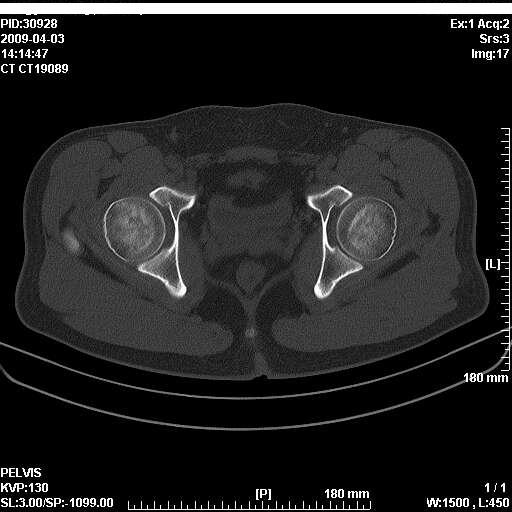

以下是引用随光逐影在2009-4-4 15:13:00的发言:[br]考虑双侧股骨头无菌性坏死;建议行mri检查进一步明确诊断。

以下是引用余辉在2009-4-4 14:22:00的发言:[br]双侧髋关节诸构成骨未见明显异常.必要时mr检查[br]患者症状已有两年,可能要同时从其他方面找原因,个人觉得不排除双侧骶髂关节有问题,建议ct检查